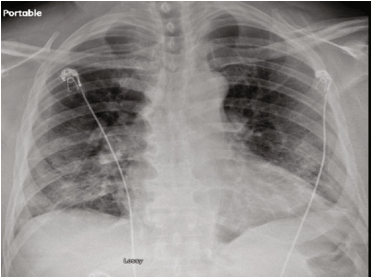

胸片显示双侧肺门周围浸润,开始服用头孢曲松进行抗生素治疗(图3)。出于对SARS-CoV-2肺炎的担忧,他开始服用羟基氯喹。患者症状在24小时内好转,2天后出院回家。出院后,诊断显示SARS-CoV-2阳性,血培养呈肺炎链球菌生长。患者被召回医院治疗菌血症和COVID-19肺炎。

图3